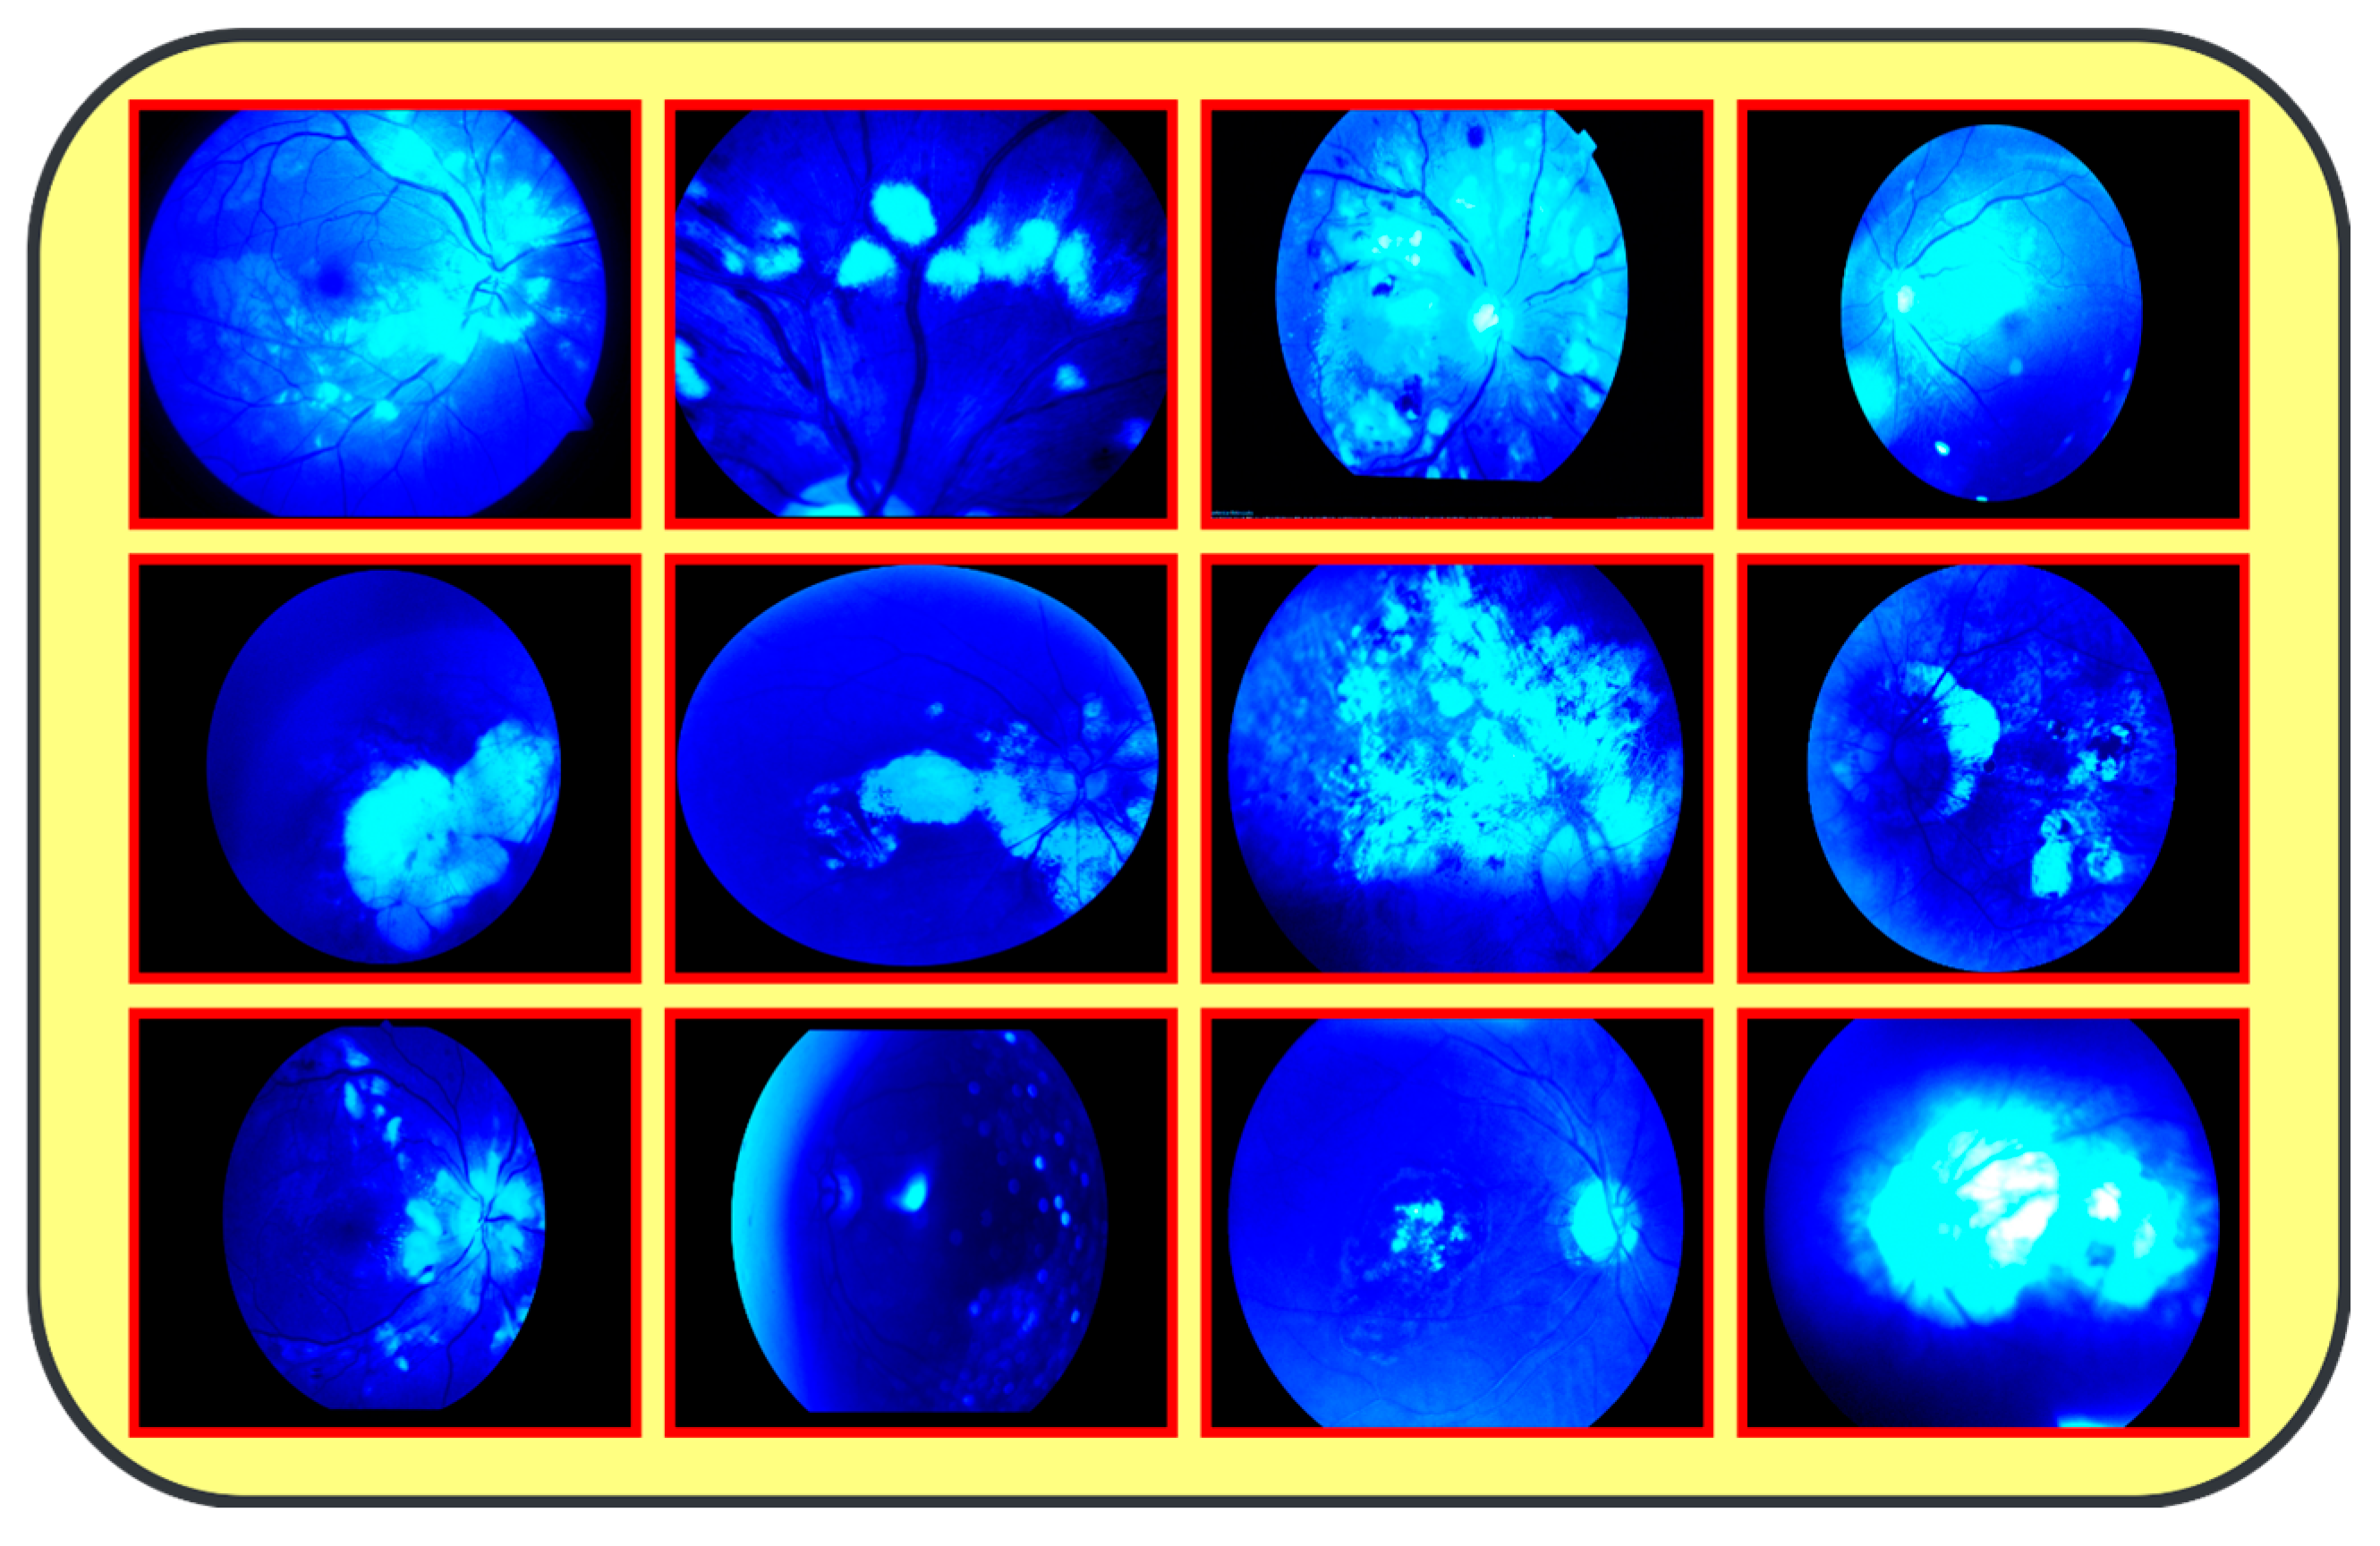

- This work is the first to introduce a Fluorescence Imaging Simulation algorithm into multi-eye classification research. The image processing algorithm along with the proposed feature fusion model allowed the model to achieve higher accuracies than reported systems while classifying four different eye diseases.

| Input Image Acquisition | Load the RGB image of the eye fundus from the dataset. All the images are normally captured with a high resolution and full color, for instance, 1125 × 1264 pixels. |

| Channel Separation | Separate the RGB image into its three color channels: red, green, and blue. Each channel is considered to be an individual gray-scale image representing the intensity of that color. |

| Green Channel Enhancement | Strengthen the green channel by scaling the intensity values with the formula G′ = α × G. Here, G is the source of the green channel, and α the scaling factor, which often takes a value of 2.0 to amplify the green’s intensity. |

| Image Reconstruction | Reconstruct the RGB image by combining the original red and blue with the enhanced green channel. I″ is given by I′ = merge (R, G′, B), where R and B are the original red and blue channels. |

| Blue Channel Suppression | This will turn off the blue channel to B = 0, which might allow the fluorescence effect to be more apparent because of the loss of the blue component but strongly showing the green fluorescence. |

| Colormap Application (Optional) | Just apply a colormap—for example, ‘HOT’—to emphasize the fluorescence more: it will just stretch the color palette of the image towards the warm end to show strongly bright green areas. |

| Output Image | Save or show the final processed image. This will shift the color scheme of the outputted image to accentuate green fluorescence and therefore pinpoint the areas of interest. |